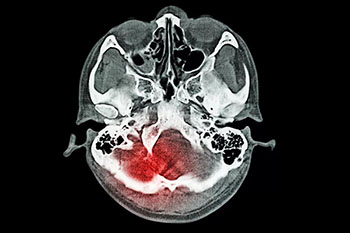

小品艺术家赵本山,09年在片场突然出现先剧烈头痛伴恶心呕吐不适,后内诊断为“蛛网膜下腔出血”,脑血管造影证实为“颅内动脉瘤”,之后接受了动脉瘤介入治疗,后康复出院,并重返舞台。

蛛网膜下腔出血是出血性脑血管病的一种,这种疾病和普通的脑出血是不一样的,普通的脑出血一般都是指脑实质内出血,而蛛网膜下腔出血,它是由于脑子里面出血,年轻患者蛛网膜下腔出血大多数都是因为颅内动脉瘤或者脑血管畸形,而老年人患这种疾病一般为动脉瘤脑动脉硬化,这种疾病的病情变化非常快,病情很危重,所以一旦出现头痛的话,可能就会对患者出现昏迷等各种的不良反应影响,严重的话,可能会危及生命。

蛛网膜下腔出血是一种症状表现,由于多种原因引起的脑血管突然破裂,是血液进入颅内或椎管内的蛛网膜下腔所引起的综合征。临床上将蛛网膜下腔出血分为自发性和外伤性两类。

常见临床症状有剧烈头痛、不同程度的意识障碍、甚至精神症状和神经功能障碍。

蛛网膜下腔出血的治疗是一项综合治疗,目的是为了防止再出血、血管痉挛及脑积水等并发症,降低死亡率和致残率。在确诊之后,应尽早进行脑血管造影或CT血管成像检查,一旦正式为颅内动脉瘤破裂,尽快准备实施开颅夹闭手术或血管内介入栓塞治疗。